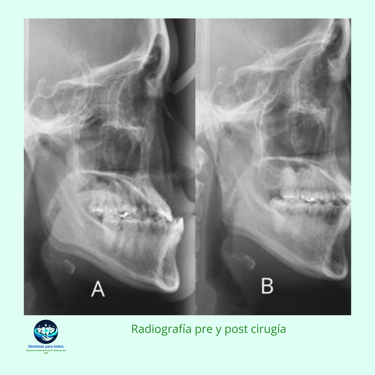

Evaluación Clínica y Radiográfica: El ortodoncista y el cirujano maxilofacial trabajan juntos para realizar un examen clínico detallado y obtener radiografías, tomografías computarizadas y modelos dentales. Esto permite planificar el movimiento preciso de los dientes y huesos.